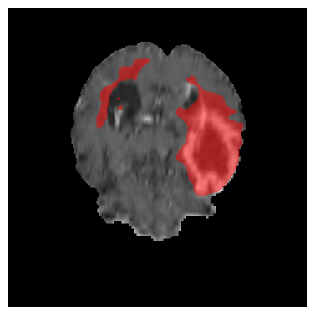

Appendix A Qualitative results

Figure 5 illustrates the segmentation evolution for the same BRATS patient in S2 sequence. The key difference here is that the best buffer-free strategy is EWC (=1), and training on BRATS data starts from episode 2 instead of episode 1 as BRATS is encountered at episode 2 in S2. The cumulative approach retains segmentation across episodes but continues to generate false positives, which become even more pronounced in the final episode. The naive approach, lacking a CL mechanisms, completely overrides previous knowledge, leading to failed segmentation in later episodes. EWC (=1) approach initially maintains segmentation but experiences a sharp decline in episode 4, where it fails to segment the tumor. In the final episode, it undersegments the lesion, missing a significant portion of the tumor. In contrast, the proposed approach consistently preserves segmentation across episodes. While initially introducing false positives, it gradually refines predictions, retaining the tumor region while minimizing misclassifications. It maintains clear tumor delineation by the final episode, demonstrating effective knowledge retention and adaptability throughout training.